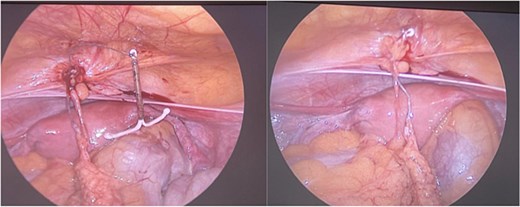

After 72 h of antibiotic therapy and clinical stabilization, she underwent a diagnostic laparoscopy. Intraoperative findings confirmed uterine perforation with the IUD partially embedded in the anterior abdominal wall amidst dense inflammatory adhesions and a localized abscess cavity. The IUD was carefully dissected free and removed. The abscess cavity was irrigated and drained thoroughly (Fig. 3).

Demonstrates the intraoperative findings during diagnostic laparoscopy. The IUD is visualized embedded in the anterior abdominal wall, surrounded by inflamed tissue consistent with a localized abscess. This confirms the diagnosis of uterine perforation and extrauterine migration of the IUD.